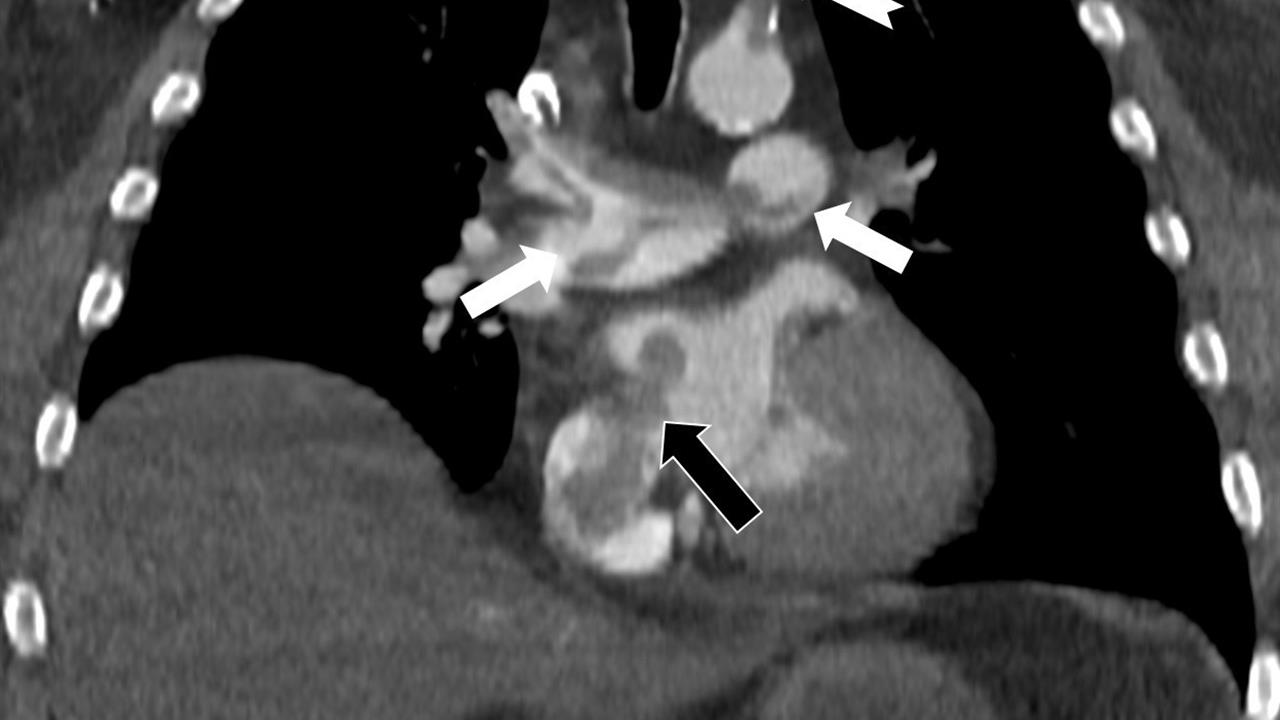

Prof. Dr. Karabulut'un çalışmasında, hastanın kalp odacıkları arasında fark edilmemiş bir delikten geçen pıhtının, hayatı tehdit eden bir durum oluşturduğu belirlendi. Bu durum, akciğerin bilgisayarlı tomografi anjiyografisi ile tespit edildi. Yapılan incelemede, pıhtının toplardamarlardan kaynaklanarak akciğer damarlarını tıkadığı, kalpteki delik nedeniyle sağ taraftan sol tarafa geçerek ana atardamara ulaştığı ve sol kol damarını tıkadığı ortaya kondu.

Emboli görüntülemesi üzerine çok sayıda bilimsel çalışması bulunan Prof. Dr. Karabulut, kalp deliği olan hastalarda ana atardamar yoluyla beyin, kol ve bacak gibi vücudun diğer bölgelerine pıhtı geçişinin ani damar tıkanmalarına yol açabileceğini vurguladı. Bu durum, paradoks emboli olarak bilinen bir durumu beraberinde getirebilir ve acil müdahale gerektirebilir.

Çalışmasında, nedeni bilinmeyen pıhtı atmalarında kalpteki gizli deliklerin mutlaka araştırılması gerektiğini belirten Karabulut, ekokardiyografi ve bilgisayarlı tomografi tetkiklerinin erken tanı koymada kritik bir rol oynadığına dikkat çekti. Bu tür tetkiklerin, hastaların yaşamını kurtarabileceği vurgulandı. Dolayısıyla, bu tür bulguların göz ardı edilmemesi gerektiği ifade edildi.